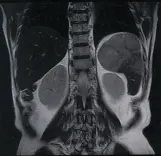

МРТ внутренних органов с возможностью онкологических исследований.

Уникальная технология – МРТ сосудов, отходящие от аорты. Сосуды почек.